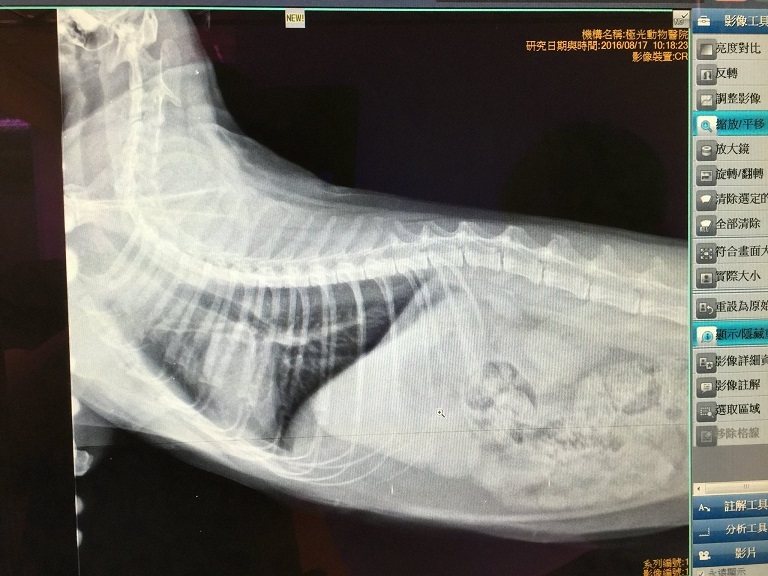

除了一般血檢、拍X光照之外,

另外也多驗了心絲蟲 (結果為陰性正常無心絲蟲感染)。

X光照片中支氣管和肺部都有稍微發炎的現象,

而血檢中比較不正常的是肝指數偏高,